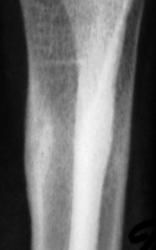

Снимки с более высокой степенью разрешения.

Определяются локальные оссифицированные периостальные наслоения в н/3 диафиза лучевой кости, что-то наподобие дефекта со склеротическим контуром по передней поверхности кости. У меня три варианта: 1 - консолидированный перелом лучевой кости; 2 - патологическая перестройка (читала у Рейнберга, может встречаться в лучевых и локтевых костях, выглядит как консолидированный перелом); 3 - первично-хр. остеомиелит.

Коллеги! меня тоже смущает участок, выделенный Валентином Львовичем стрелочками. Имеются округлой формы, мелкие участки перестройки костной ткани литического типа. Кортикальный слой муфтообразно утолщен с периоссальной реакцией. А нет ли там объемного образования?

Меня тоже смущает, и очень. Отправляйте к детским онкологам, пусть они контролируют. Основание: диафиз лучевой кости бульбообразно расширен ("поддут"), структура кости уплотнена муфтообразно/"пояском", менее выраженные, чем по переднему стенке кости, но аналогичные изменения отмечаются и по задней стенке диафиза, плюс периостальная реакция в прямой проекции.